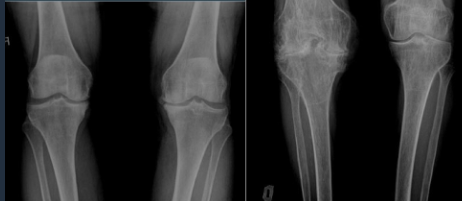

Knee

Gonarthrosis

Arthrosis Rx

GENERAL Rx signs

Joint space narrowing (even or uneven)

Subchondral OS

Subchondral cysts

Osteophytes

Technique: 2 views AP + prophyle

CHANGES

Joint space narrowing : slow, expressed in %

Osteophytes: marginal, subcartilaginous

Subchondral OS & subuxation

Synovitis: joint effusion (US, MRI)